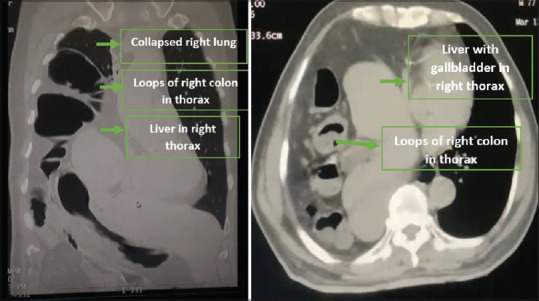

Abstract: Diaphragmatic eventration (DE) is an abnormal condition where a portion or the entire hemidiaphragm elevates due to insufficient muscle or nerve function while maintaining its anatomical attachments. On the other hand, congenital diaphragmatic hernias occur due to the abnormal development of muscular entities of the diaphragm, resulting in the displacement of abdominal contents into the thorax. The difference between diaphragmatic hernia and eventration is important as there is no true defect in DE. Ruptured eventration of the diaphragm is a rare entity, with only three cases reported in adults in literature till date, all on the left side. We report the first case of ruptured eventration of the diaphragm on the right side, which was repaired by a combination of laparoscopy and thoracoscopy and with double-mesh placement.